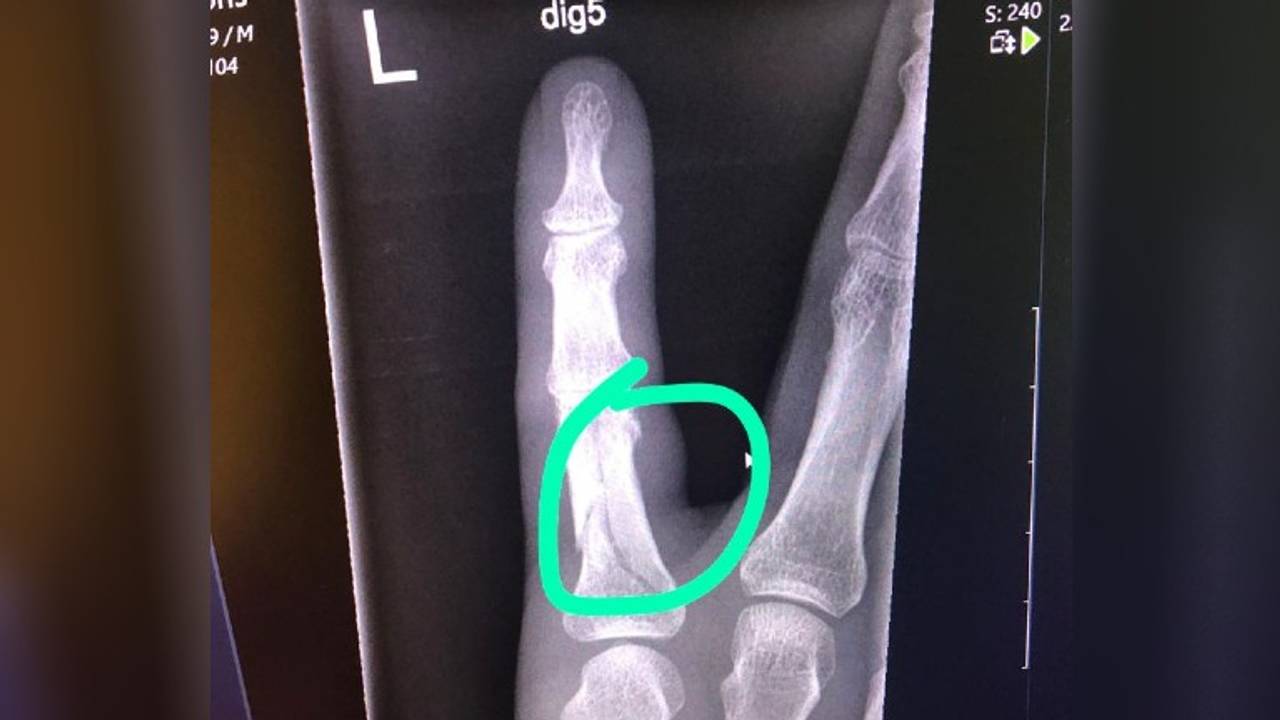

Het algoritme ontdekte tijdens de testfase, waarin het zeshonderd recente foto's analyseerde, zelfs zeven breuken die door professionals niet waren opgemerkt.

"Uit onze test bleek dat BoneView in staat is om fracturen te vinden die de specialisten met het blote oog niet zagen", zegt radioloog Erik Ranschaert. Als de onderzoeksresultaten worden doorgetrokken naar een heel jaar, zouden in het ziekenhuis per jaar 360 tot 370 gemiste breuken opgespoord kunnen worden, voegt hij eraan toe. "Dat is toch een aanzienlijk aantal."

De software beoordeelt in 3 minuten een röntgenfoto en kan in de meeste gevallen met zekerheid zeggen of iemand een fractuur heeft. De uitkomst kan ook 'twijfel' zijn. Dan staat er een stippellijn op de plek waar de mogelijke breuk zit en moet de radioloog alle foto's goed bekijken en zelf de knoop doorhakken.